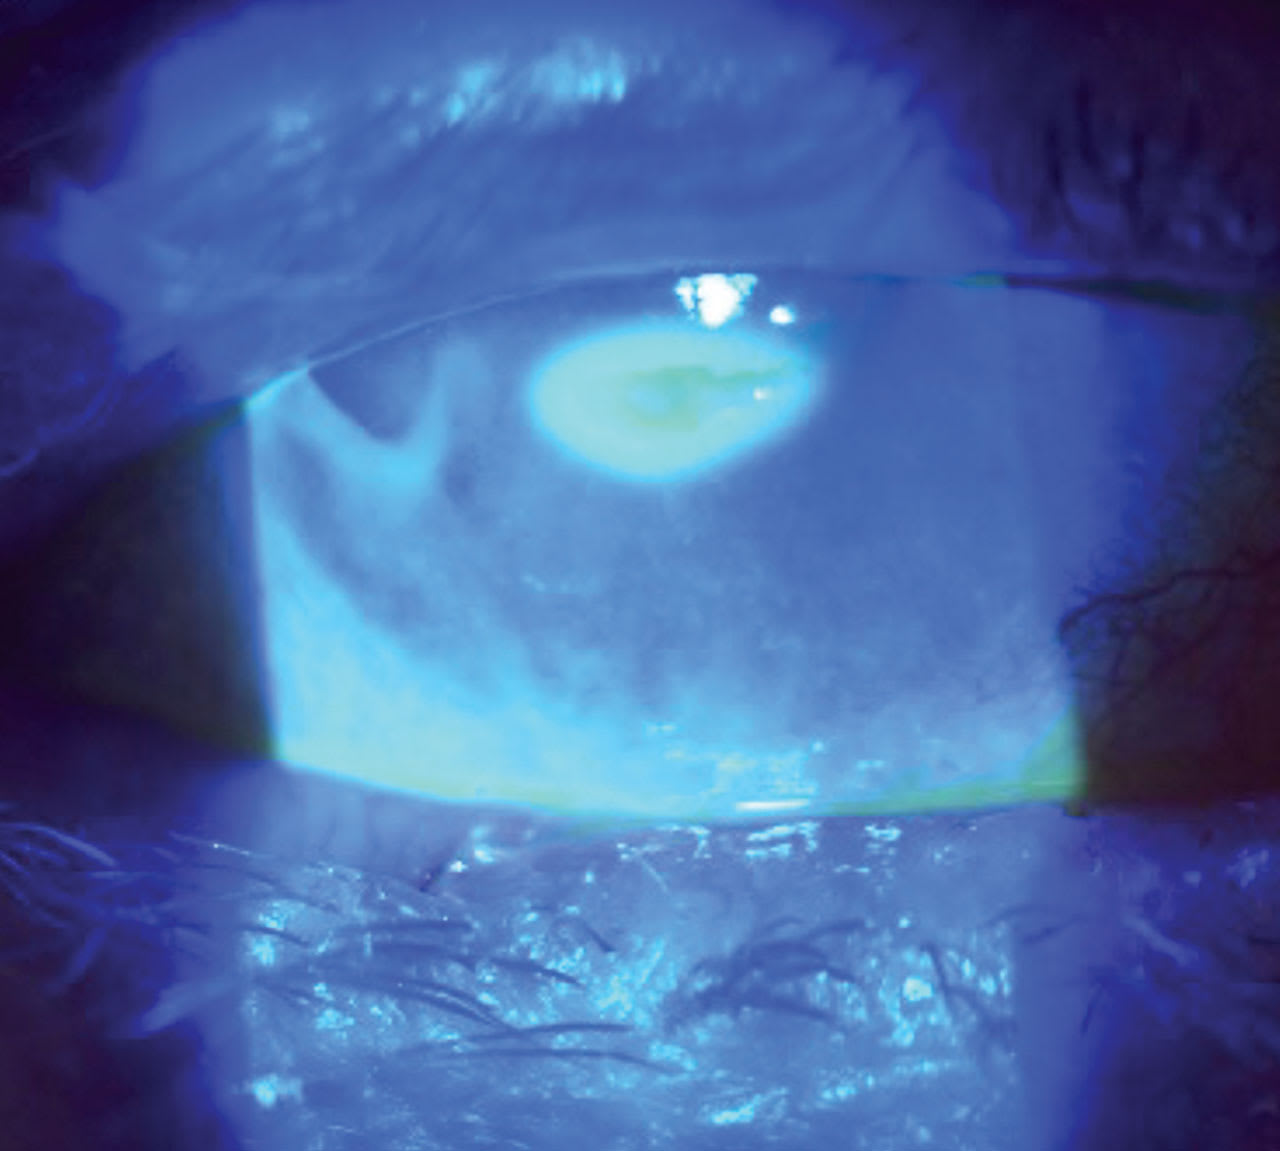

A 44-year-old male presented to the clinic with a chief complaint of severe pain, along with photophobia in his right eye for the past few days.

• Patient ocular history: ectasia secondary to laser-assisted in situ keratomileusis (LASIK) surgery for the past few years. The patient admitted to sleeping in his scleral contact lenses. Figure 3 displays the anterior segment image.

• Diagnosis:

1) corneal ulcer

2) ectasia

• Treatment: Approaching a compromised cornea with underlining conditions such as keratoconus or post-refractive complications must be aggressive but guarded. In this case, it was a cryopreservative slim-profile amniotic membrane, besifloxacin q.i.d. to the affected eye, and artificial tears every 30 minutes. Figure 4 shows the eye with an AMCL over the compromised cornea. Figure 5 shows an image three days after removal.